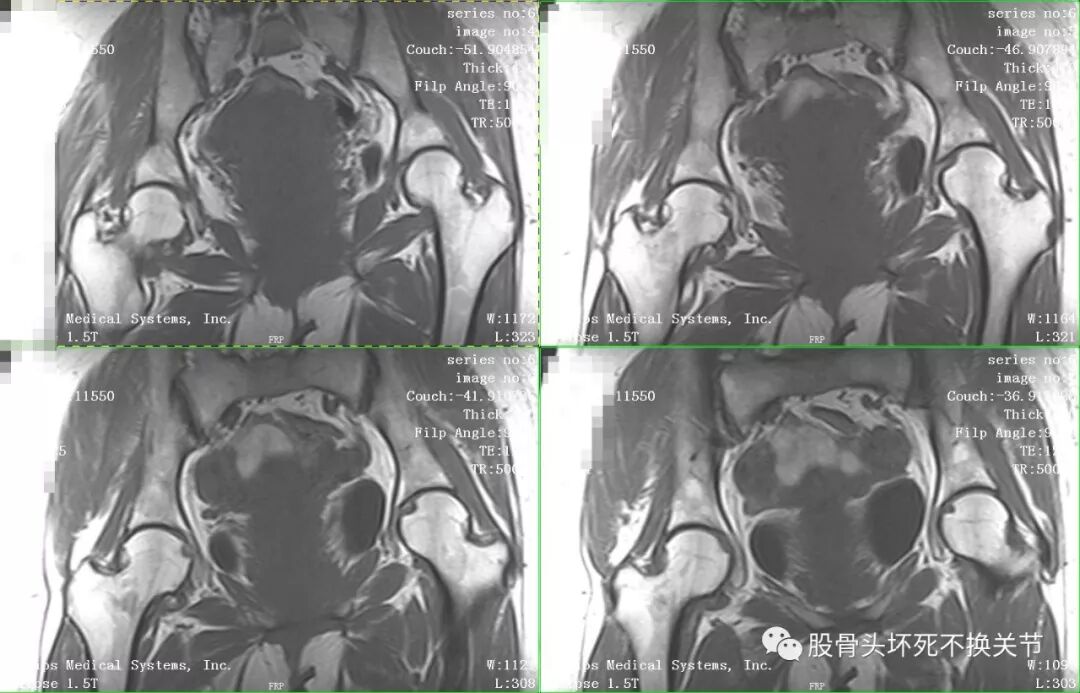

核磁共振是诊断疑难疾病的必备检查,更是诊断滑膜炎最直观、生动的手段。

点击放大观看双侧髋关节核磁共振片:

核磁共振检查显示右侧股骨头周围一圈亮度均匀的白色信号,就是平常所说的关节积液。